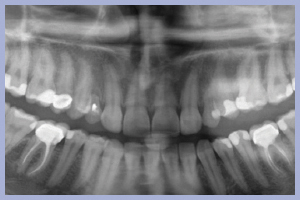

- Figg. 9a, b – Preparazione del sito di destra

- Figg. 10a, b – Preparazione del sito di sinistra

Dopo l’estrazione, eseguita con i consueti passaggi di scollamento-lussazione-estrazione, la revisione chirurgica tramite cucchiaio alveolare consentiva la completa rimozione dei frustoli di tessuto di granulazione e di legamento parodontale residuo. La preparazione del sito implantare veniva effettuata con approccio flapless, ovvero senza l’esecuzione del lembo.

Una volta determinato, sul versante palatale dell’alveolo, il giusto asse di preparazione, si lavorava fino alla profondità programmata; la sequenza di frese comunemente impiegate per il diametro implantare da posizionare completava la preparazione dell’alveolo chirurgico. Non era richiesto l’uso della fresa svasatrice dal momento che a livello cervicale l’alveolo presentava un diametro maggiore di quello implantare.